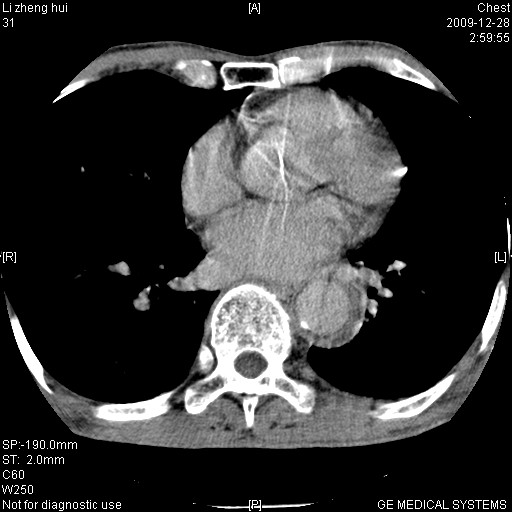

男  79岁 胸部痛急诊入院,晚上做的增强

考虑主动脉瘤?(增粗、钙化、壁血栓?)

动脉瘤伴附壁血栓

1)考虑胸主动脉壁间血肿或夹层动脉瘤。2)多发性肝囊肿。

1)考虑胸主动脉附壁血栓或夹层动脉瘤。2)多发性肝囊肿。

考虑大动脉炎,附壁血栓形成。